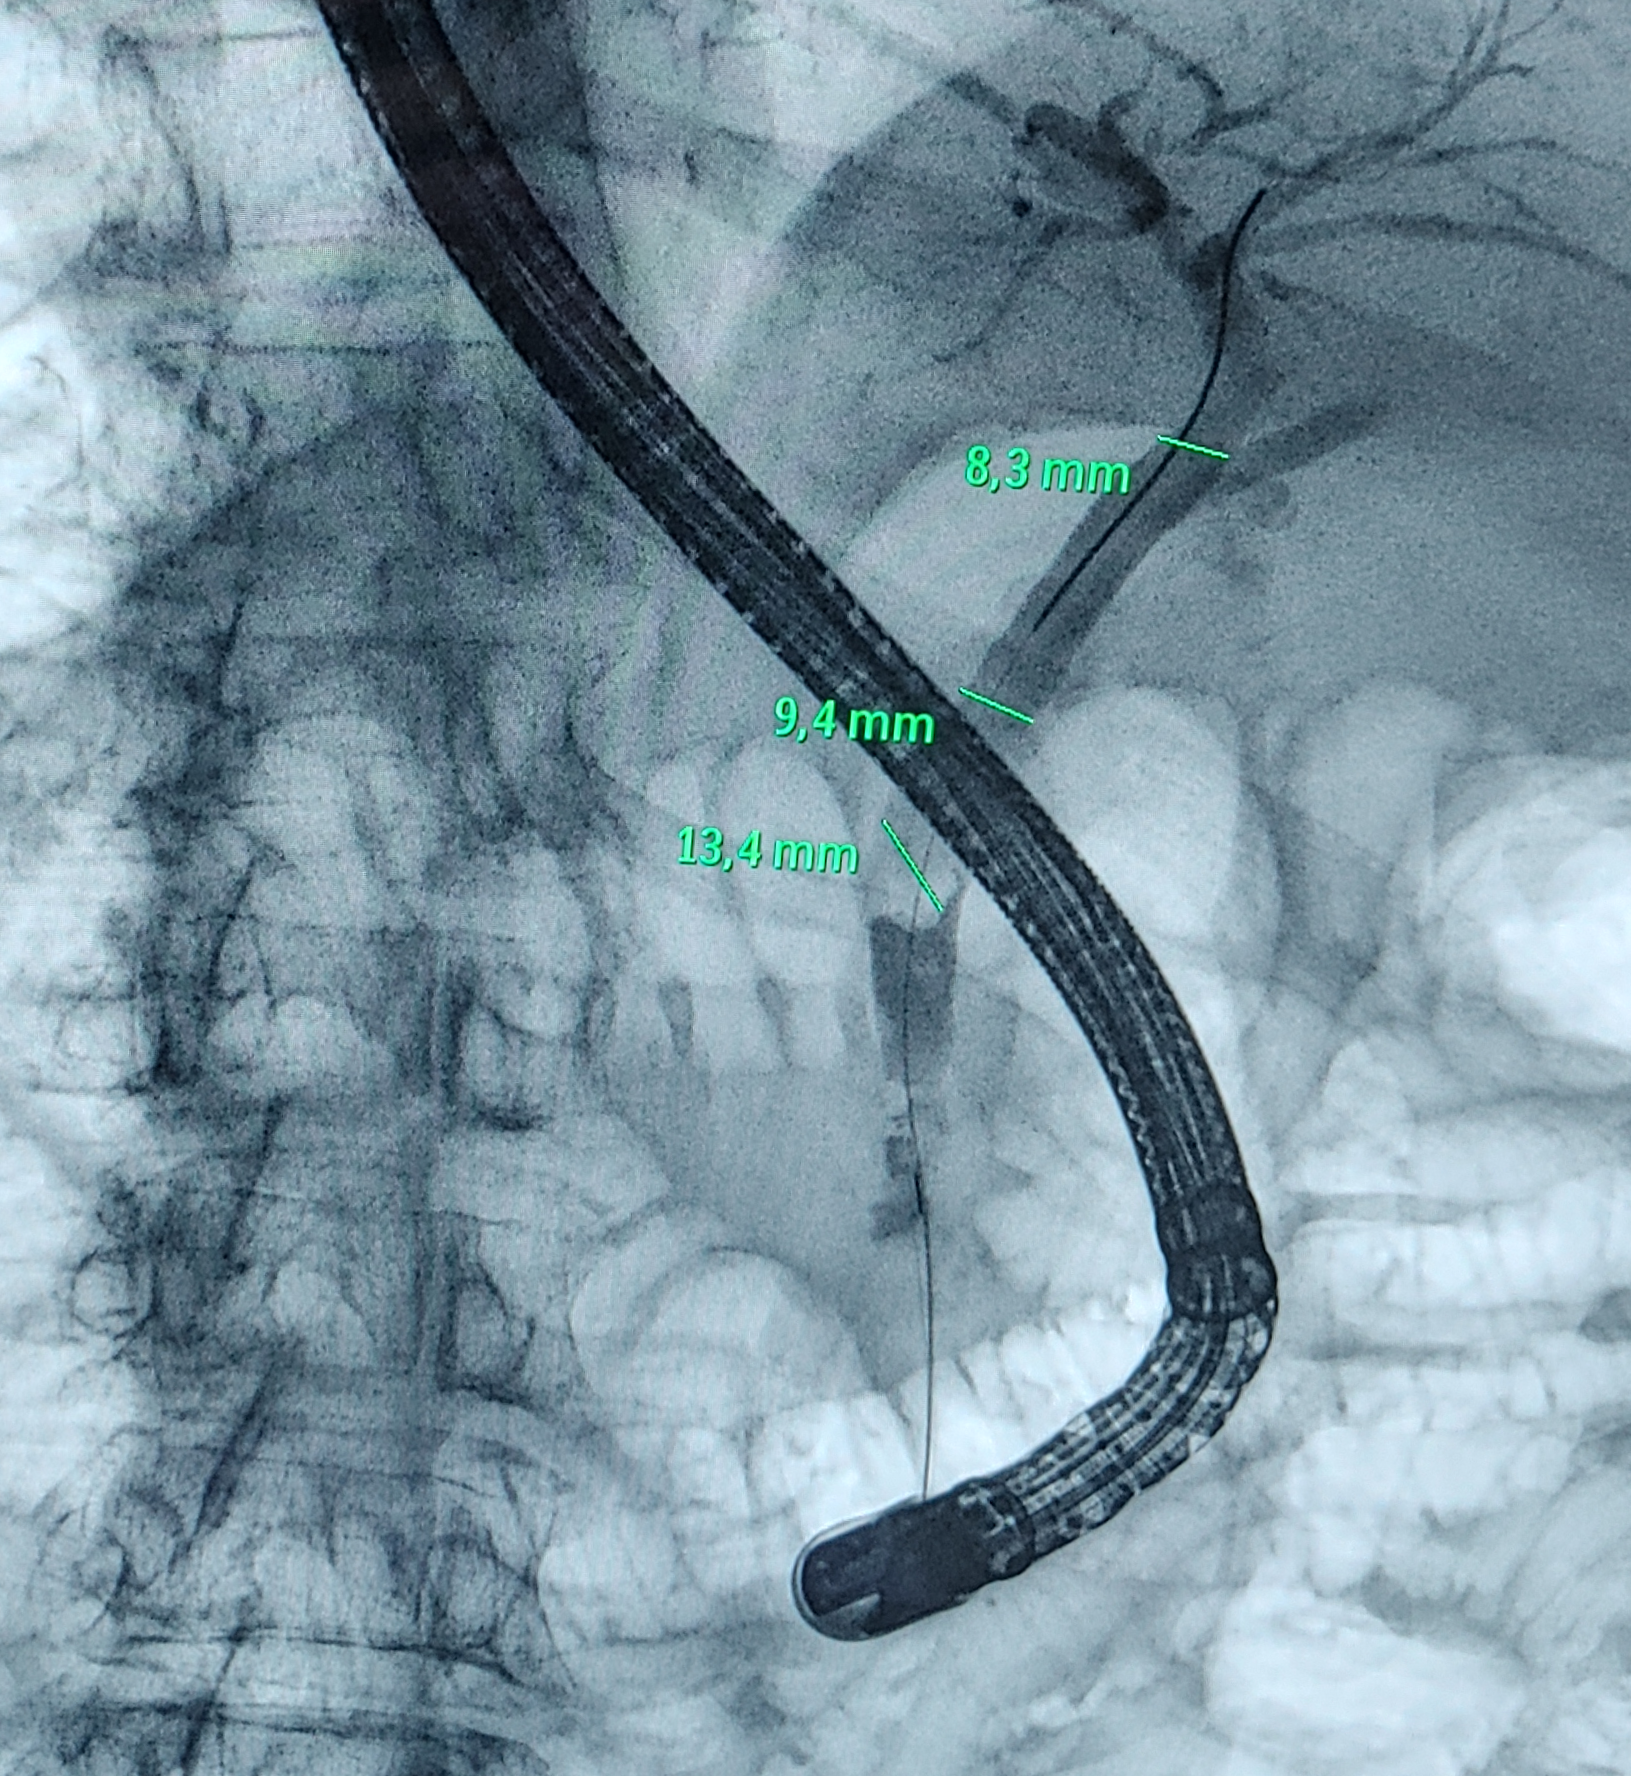

Biliar - CPRE

Extracción de Cálculos Biliares

Extracción Cálculos Pancreáticos

Protesis Biliares Transitorias - Permanentes

Prótesis Pancreática

Dilataciones

Esofágica - Pilórica - Biliar

Bilioplastia